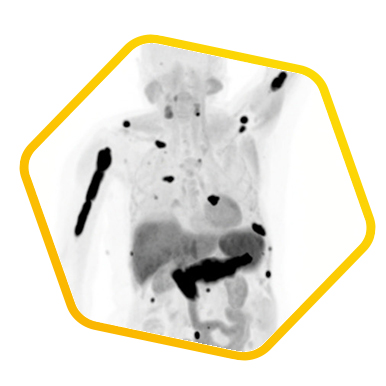

Prostate Cancer

![]() [F-18] PSMA |